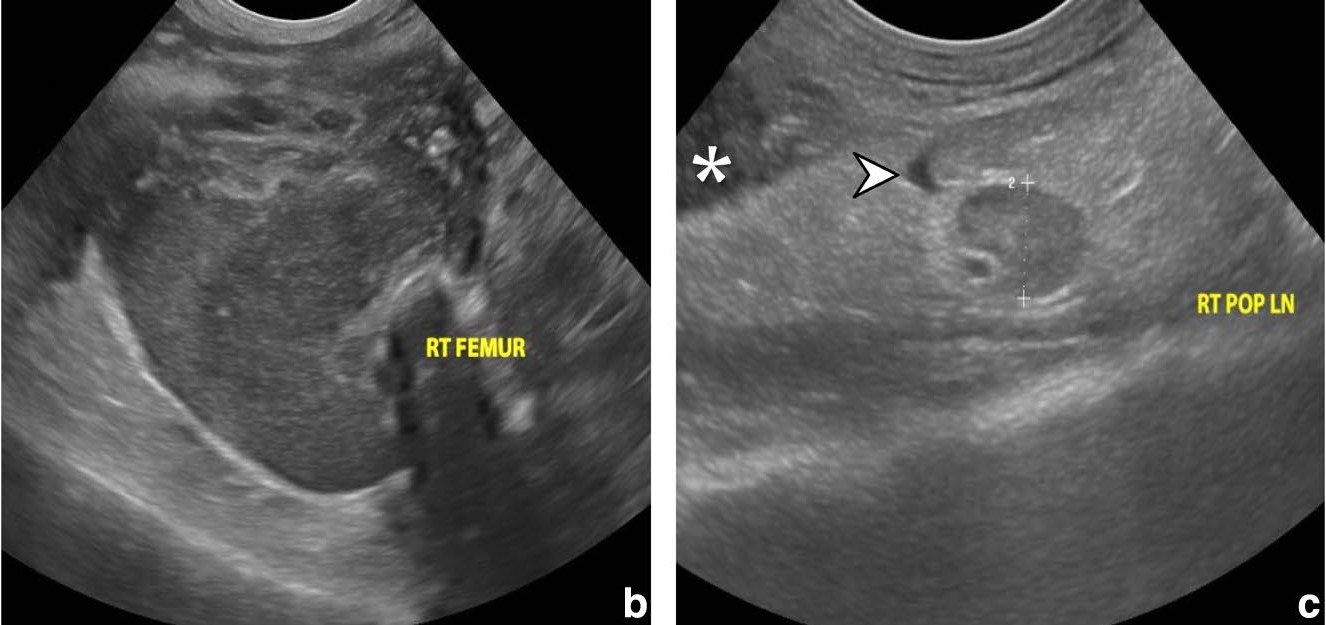

双眼角膜荧光素染色阴性。眼压:左眼20 mmHg,右眼90 mmHg。右眼超声显示虹膜与睫状体后方有一大而回声强的“肿块”(图2a),玻璃体腔无明显改变,无视网膜脱离。

图2. 超声图像:(a) 右眼,显示一个增大的高回声肿块(白色星号),从虹膜延伸至晶状体后囊。

右后肢肿胀处超声示股四头肌增厚、回声增强并周围水肿(图2bc)。肌内穿刺细胞学符合大细胞、高级别淋巴瘤。腹部超声示脾、胰腺增大,但脾穿刺未见恶性证据。

图2. (b) 右侧股四头肌,肌肉增厚且回声增强,周围伴水肿,肌筋膜界限不清;(c) 右侧腘淋巴结,大小和形态正常,但周围可见少量游离液体(白色箭头)。注意水肿已延伸至大腿后侧肌肉(白色星号)。